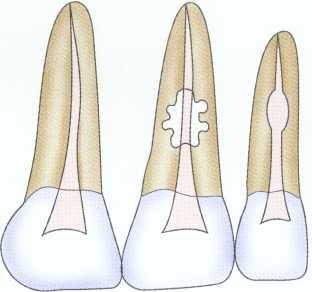

Radiographic examination of the hard tissues can often provide valuable information regarding caries and existing restorations, calcifications, internal and external resorptions, tooth and pulpal morphology, root fractures, the relationship of anatomic structures, and the architecture of the osseous tissues (Figure 1-16). In addition, radiographs can be used to trace sinus tracts ,27 demonstrate periodontal defects, and diagnose resorptive lesions (Figure 1-17). However, they do have many limitations and are of little value in assessing pulpal status. Vital and necrotic pulps cast the same image. Moreover, radiographs are only two-dimensional images of threedimensional structures.

FIGURE 1-16 Radiographic examination generally requires a periapical projection, although bite-wings and pantomographic projections are often useful. In this case the periradicular tissues appear normal; however, a comparison of the root canal space of #8 and #9 reveals that the space in tooth #9 is considerably larger. This is consistent with the clinical presentation, symptoms, and diagnostic testing results, which indicate necrosis.The radiographic appearance of the root canal system is caused by the lack of secondary dentin formation overtime.

FIGURE 1-17 Radiographs are useful in diagnosis. External resorptive defects such as the one depicted in the maxillary left central incisor are often irregular, with the root canal coursing through the lesion. Internal resorption such as that depicted in the maxillary eft lateral incisor is often symmetric and exhibits destruction of the canal wall. In addition, internal resorptive lesions remain centered on angled radiographs.

Periapical radiographs and other images should be exposed using a positioning device and a paralleling technique. This provides the most distortion-free image and accurate diagnostic information. Although great emphasis is often placed on the radiographic examination, it is an imperfect diagnostic aid because of the varied techniques and methods for obtaining the film or image and the variable ability of practitioners to interpret the information correctly.28-30 Subtle and moderate changes are often difficult to detect early in the pulpal and periradicular disease process. As the disease progresses, lesions become more distinct and easier to detect. Evidence suggests that a periapical lesion must erode the cortical plate to be visible on the film or image. 31 Making a second film using an angled projection can increase the diagnostic accuracy.32 2

Periradicular lesions resulting from pulp necrosis have a characteristic appearance. The radiolucency exhibits a "hanging drop" appearance, with the lesion beginning on the lateral osseous surfaces of the root and extending apically into the osseous tissues. The lamina dura is absent, and the lesion does not move when angled films are taken. In general, a radiolucent lesion associated with a tooth with a vital pulp is not of endodontic origin.